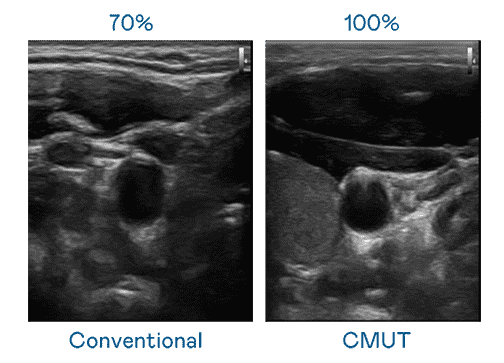

CMUT 技术是一种用电容式微机电元件来产生超音波讯号的技术。。。。与传统 PZT 压电式技术相比,,,,CMUT 频宽增加 30%,,,更宽频的超音波讯号让影像解析度大幅提升,,是实现高影像品质医疗超音波扫描、、、、促进精准医疗发展的关键技术。。。。

大频宽带来超清晰影像

超音波影像的解析度高低,,,首先取决于探头能发出的讯号频宽。。。。赏金国际 CMUT 可提供高清晰的超音波讯号,,,提供高频宽、、、高灵敏度、、影像纹理细节更高的超音波影像,,,协助医护人员缩短影像判读时间及利用精准的医疗影像进行诊断。。。。